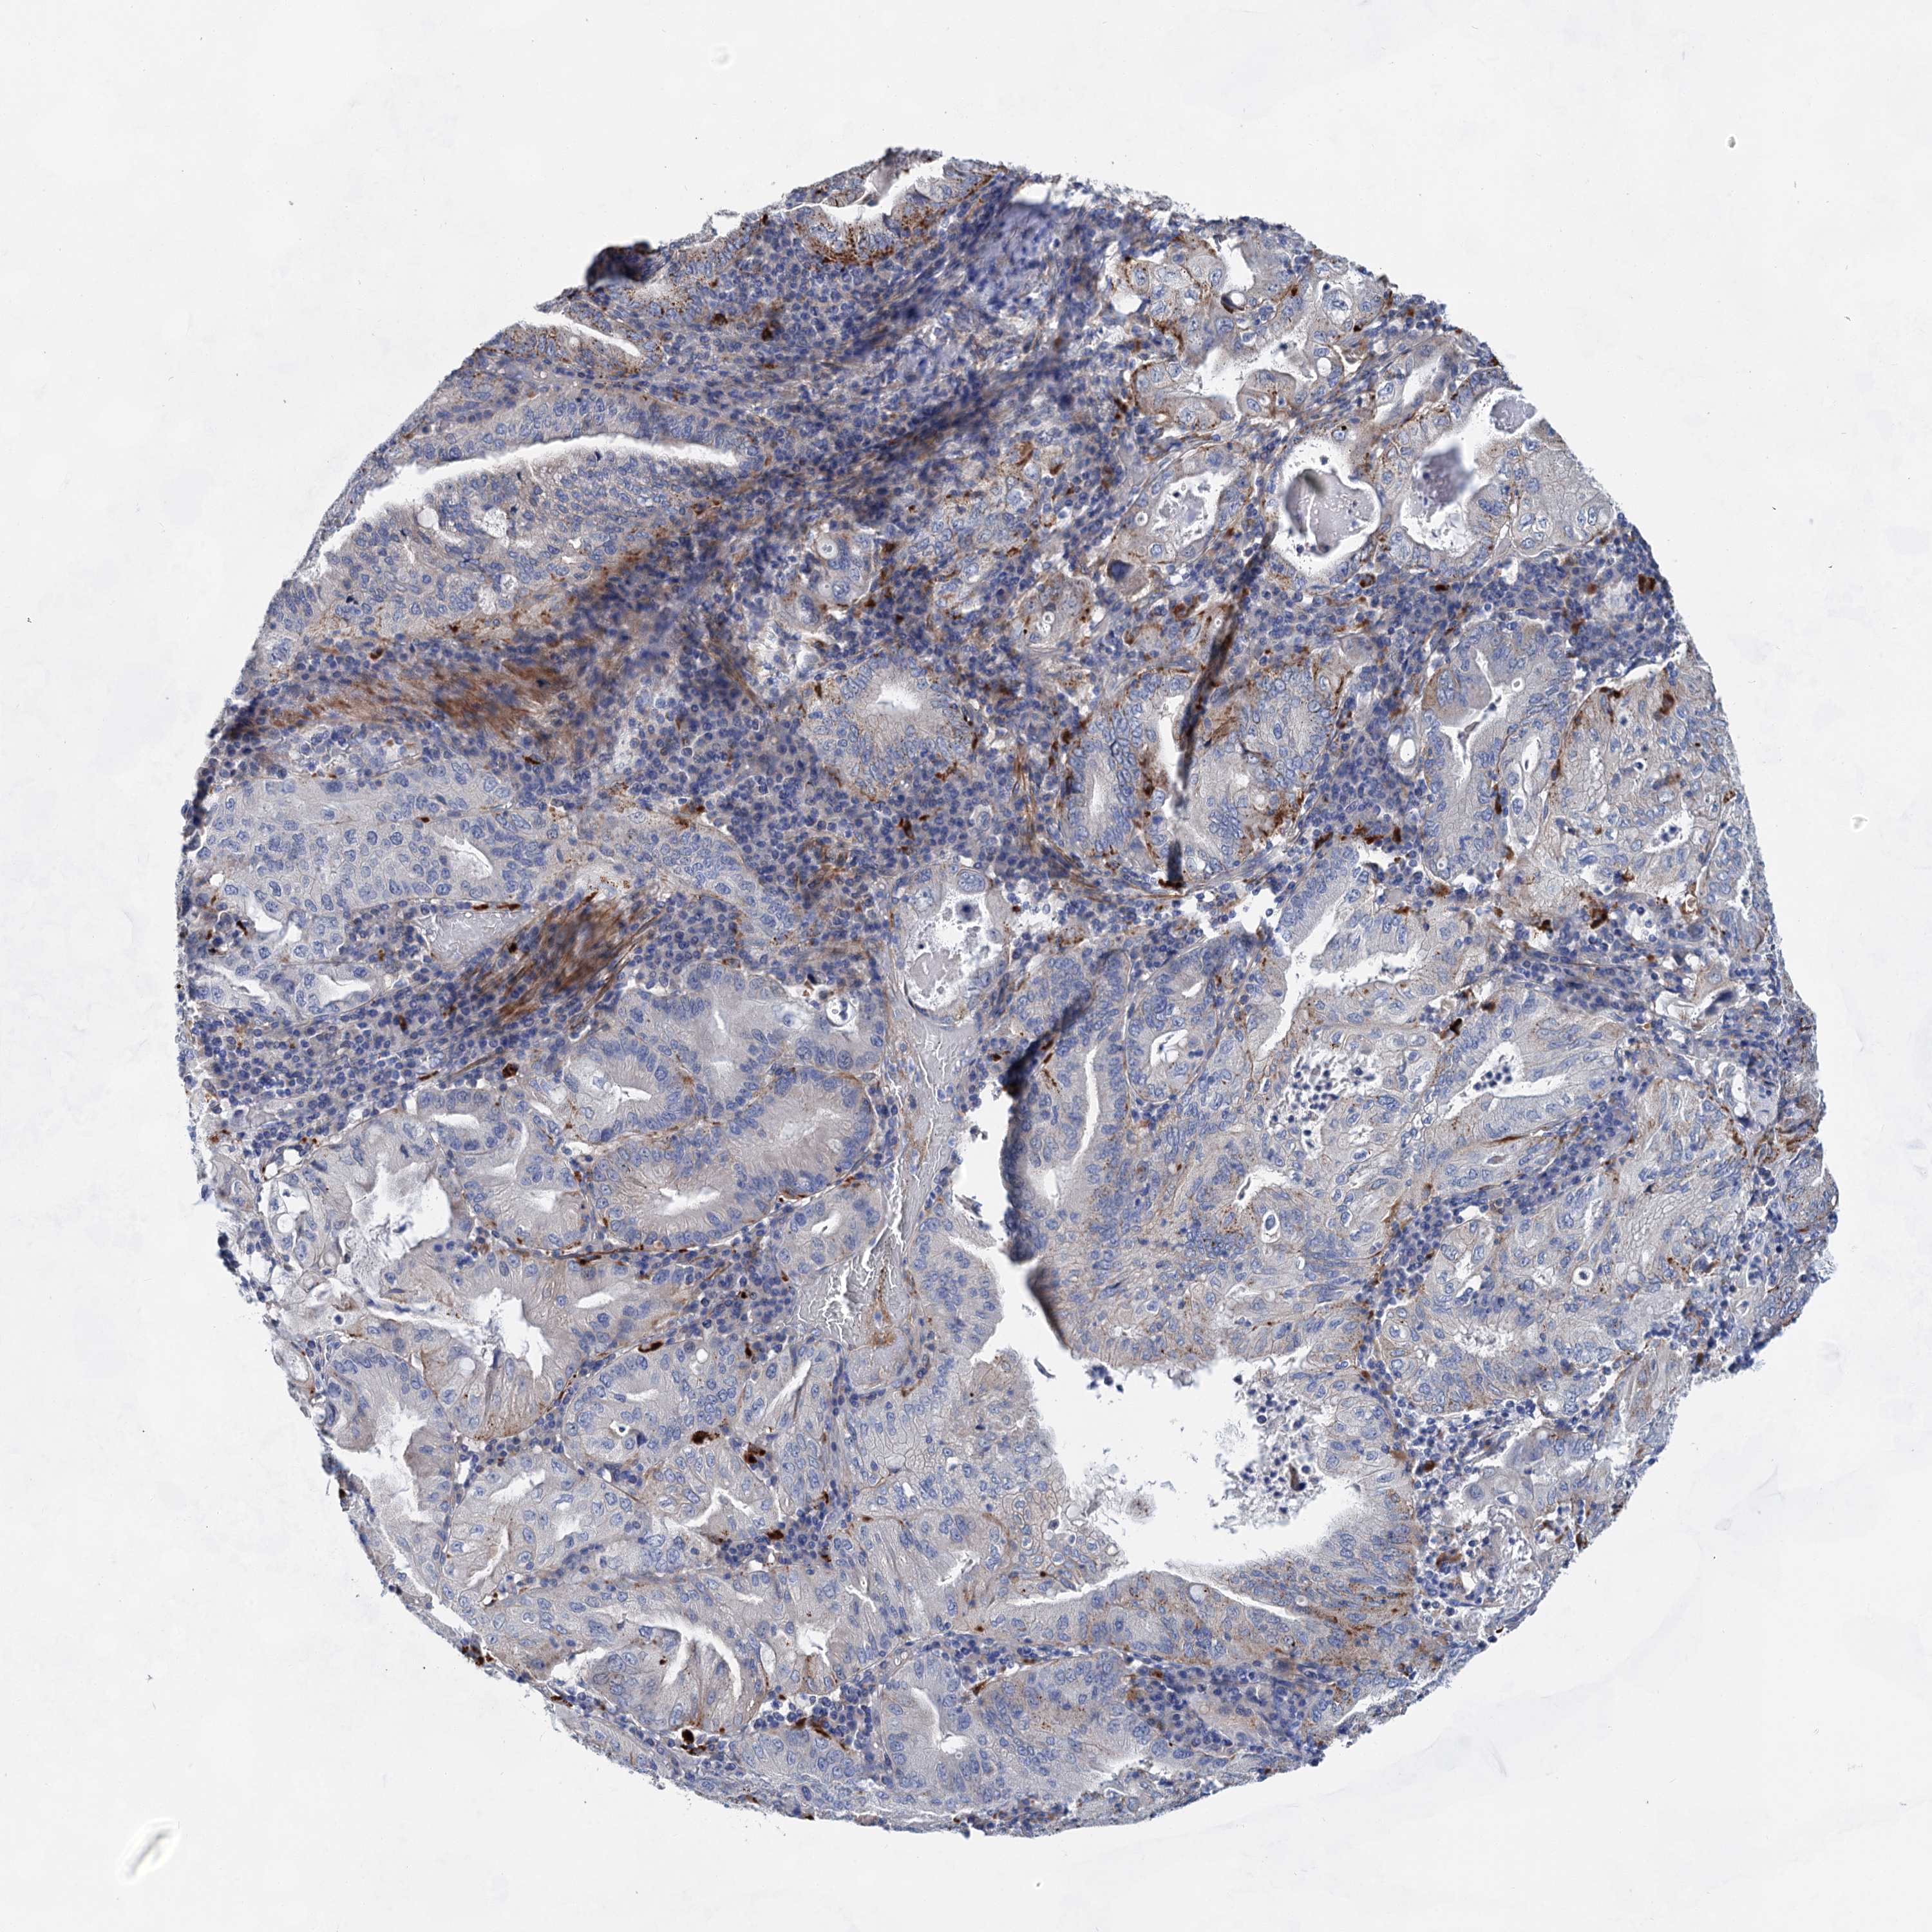

STOMACH CANCER - Protein expressioni

A mouse-over function shows sample information and annotation data. Click on an image to view it in a full screen mode. Samples can be filtered based on level of antibody staining by selecting one or several of the following categories: high, medium, low and not detected. The assay and annotation is described here.

Note that samples used for immunohistochemistry by the Human Protein Atlas do not correspond to samples in the TCGA dataset.

Antibody stainingi

Antibody staining in the annotated cell types in the current human tissue is reported as not detected, low, medium, or high, based on conventional immunohistochemistry profiling in selected tissues. This score is based on the combination of the staining intensity and fraction of stained cells.

Each image is clickable and will lead to virtual microscopy that enables deeper exploration of all samples and also displays staining intensity scores, fraction scores and subcellular localization as well as patient and tissue information for each sample.

Antibody HPA036159

Antibody HPA057384

Staining

High

Medium

Low

Not detected

Intensity

Strong

Moderate

Weak

Negative

Quantity

>75%

75%-25%

<25%

None

Location

Nuclear

Cytoplasmic/membranous

Cytoplasmic/membranous,nuclear

Adenocarcinoma, NOS

Adenocarcinoma, High grade